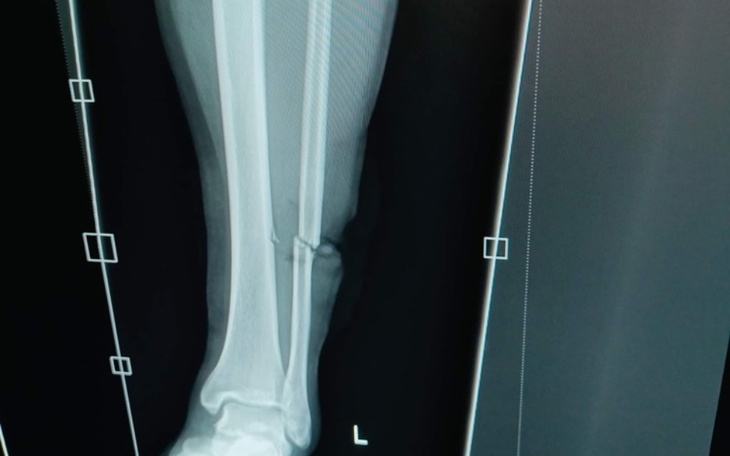

Nazywa się Julia. W sierpniu tego roku,mój najdroższy młodszy brat uległ okropnemu wypadkowi. Został napadnięty podczas powrotu do domu. Napastnik zaatakował go maczeta. Dawid ma tylko 20 lat a już niestety został okaleczony do końca życia. Trudno wiązać mi koniec z końcem bo sama się nim zajmuje. Nakładające się rachunki oraz leczenie wykańczają mnie do końca. Podczas wypadku Dawida nie został on okaleczony tylko fizycznie ale niestety również psychicznie. Mój brat nie radzi sobie z sytuacja,która nas spotkała. Blagam o wszelka pomoc finansowa abyśmy mogli dalej rehabilitować nogę oraz udać się na terapie psychologiczna. Będę wdzięczna za każda pomoc. Dziękuje.